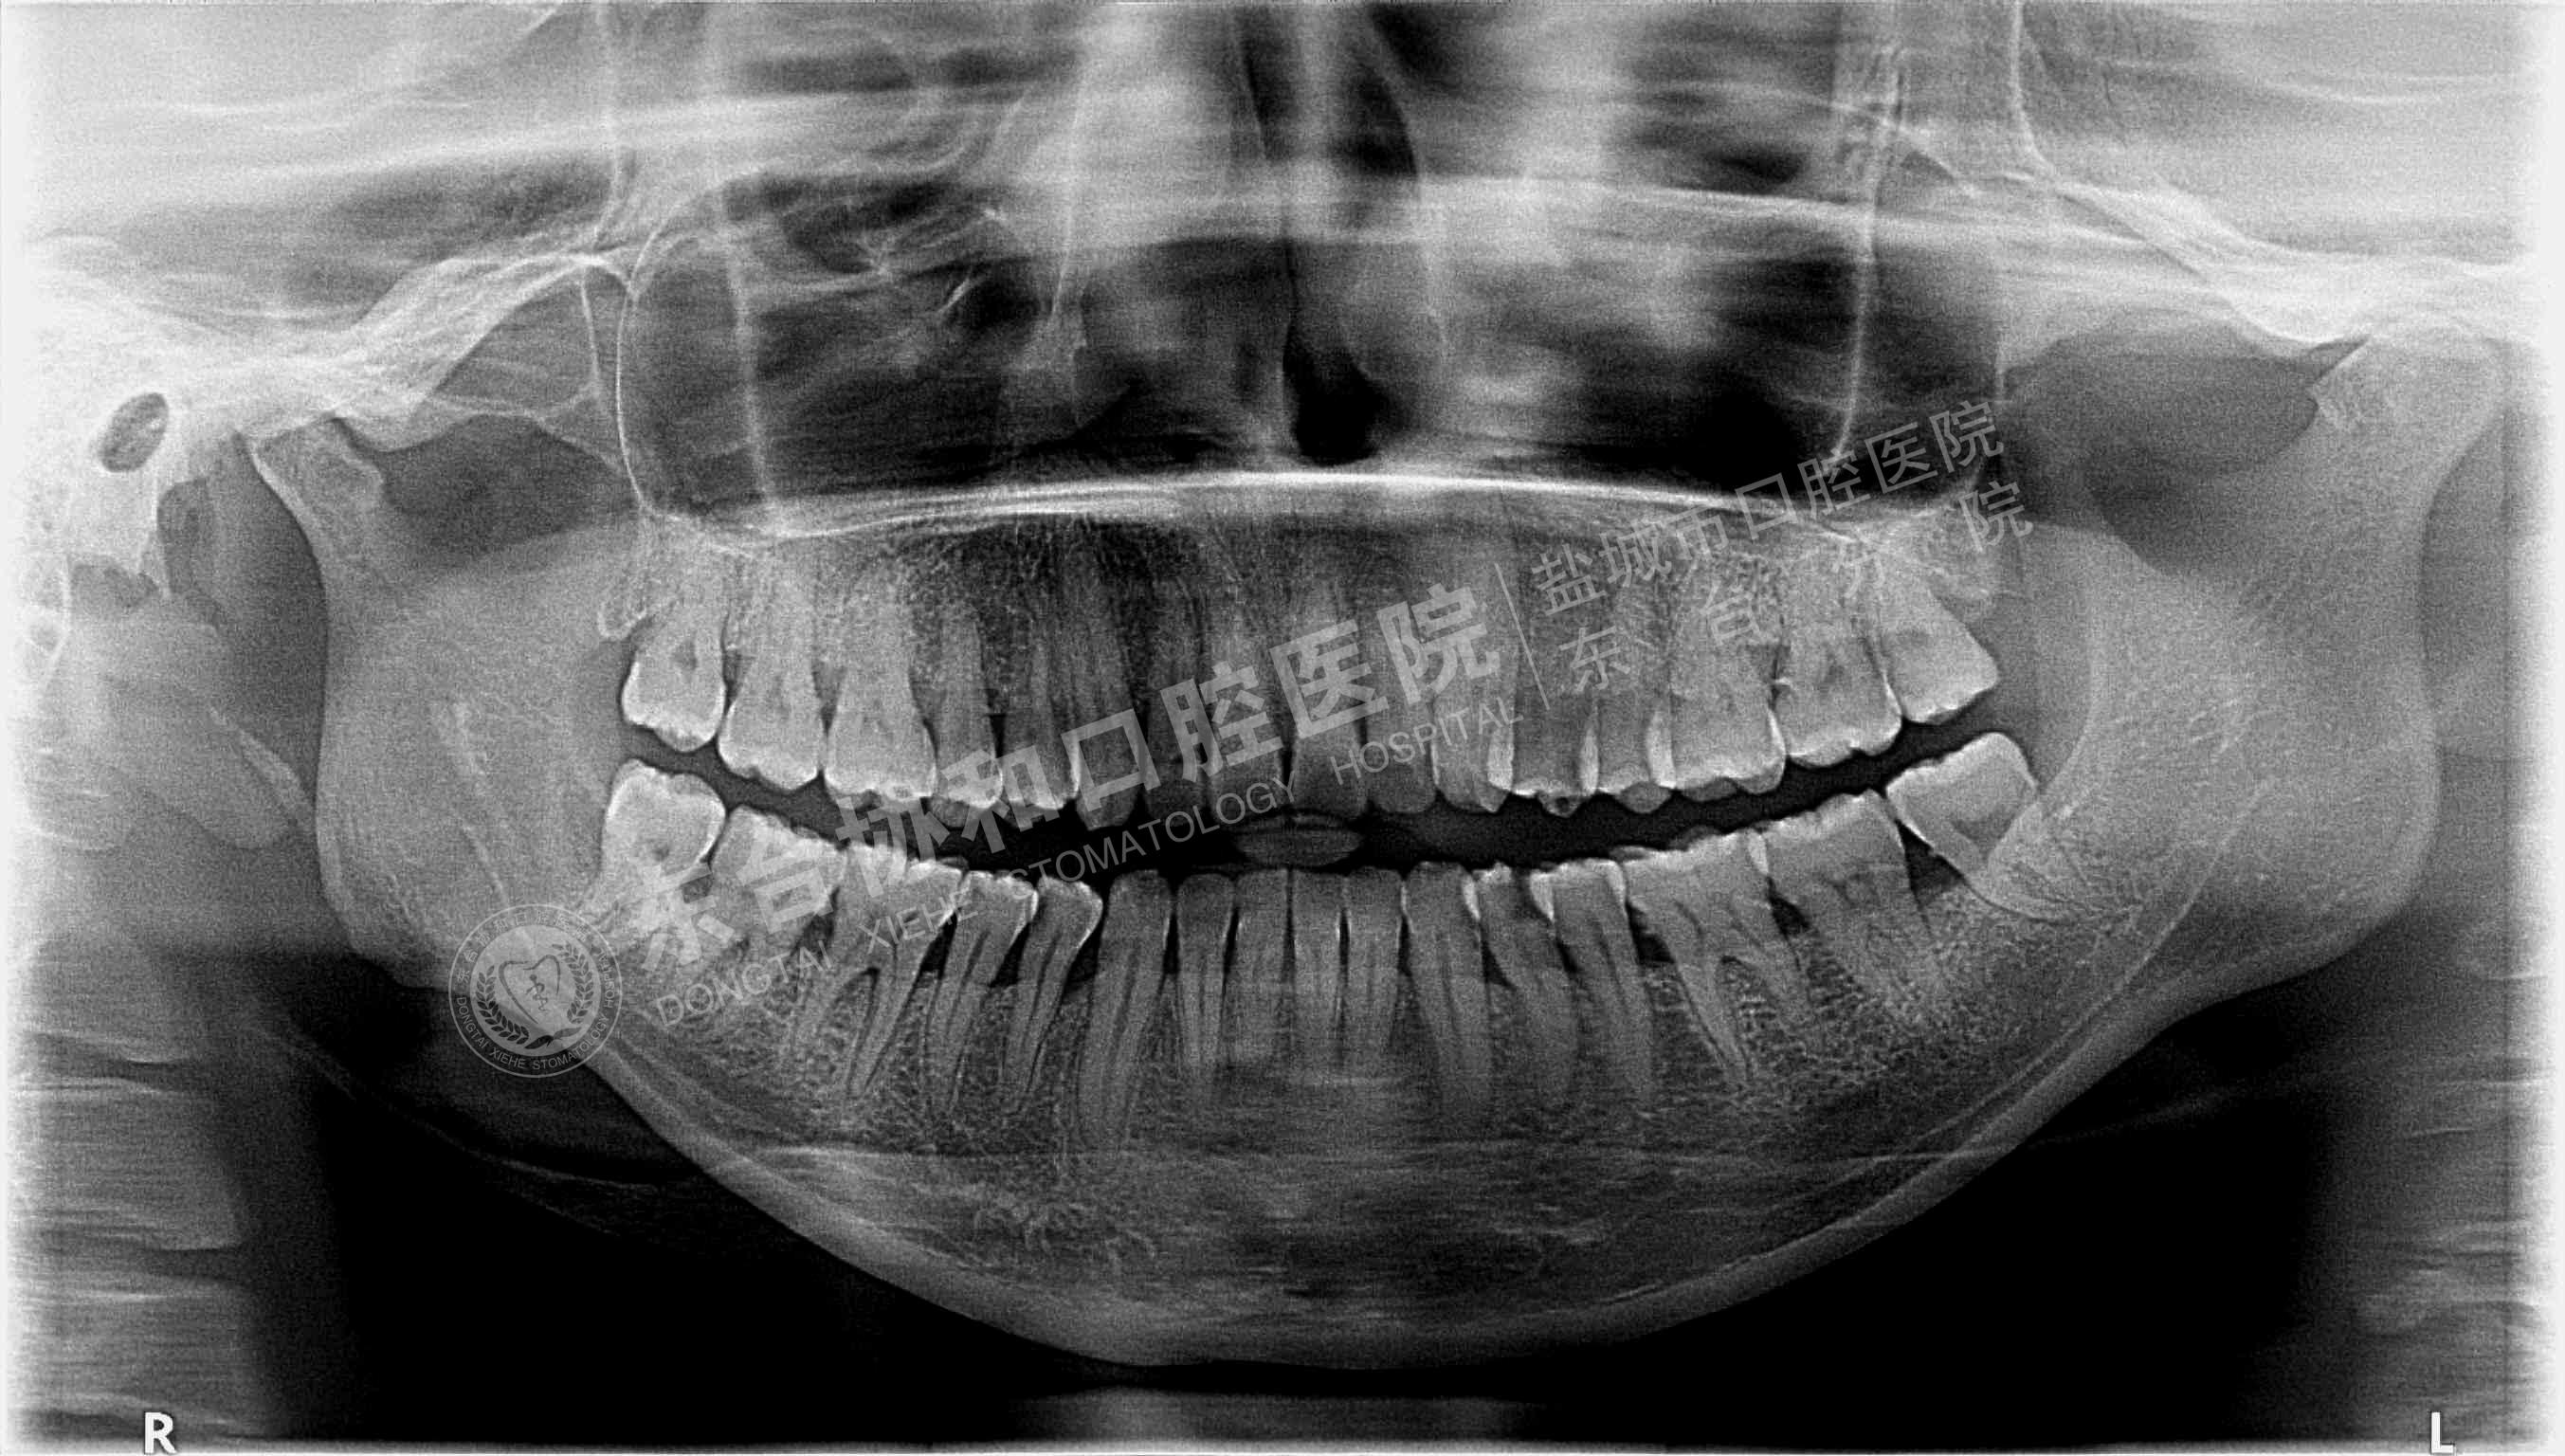

很多患者都很排斥拍牙片,認(rèn)為醫(yī)院是為了多收錢才讓他們拍的,其實(shí)這是一個(gè)錯(cuò)誤的想法,拍牙片是口腔科常用重要的檢查手段,臨床檢查只能直觀判斷牙冠和牙齦部分的情況,而對(duì)于牙根,牙槽骨、牙周膜等情況則必須通過牙片檢查。牙齒在牙片上顯示出白色阻射影像,其中牙釉質(zhì)阻射強(qiáng),牙本質(zhì)和牙骨質(zhì)阻射低于牙釉質(zhì),牙髓腔呈灰黑色影像,根管口至根尖孔呈逐漸變細(xì)的影像。

通過牙片除了了解牙齒的病變情況,還可以了解牙槽骨內(nèi)是否有埋伏牙、多生牙、牙源性腫瘤和囊腫等,依據(jù)牙片綜合分析可以提高牙齒診斷調(diào)節(jié)的準(zhǔn)確性和。

5、牙周炎癥:顯示牙槽骨吸收范圍和破壞程度。

8、牙齒矯正:拍攝口腔全景片和頭顱側(cè)位片,以檢查骨骼和牙齒的發(fā)育情況。

10、種植牙拍牙片顯示牙槽骨的健康狀況、高度、密度,是否適合于種植牙;種植體的成活情況。